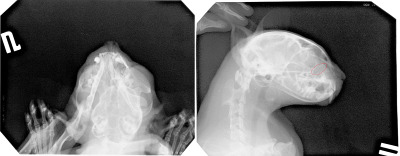

Выкладываю два рентгеновских снимка моей кошки. На одном из них кошка лежит на пластине правым боком. Другой снимок - она лежит на пластине подбородком (не совсем ровно, правда). На снимке сбоку опухоль обведена красным. На другом снимке не стал обводить, т.к. боюсь соврать - не вижу точно, где то место.

Симптомы: началось с того, что начал постоянно слезиться левый глаз (впервые это заметил в июле - начале августа). Потом на мордочке с левой стороны носа появилась небольшая шишка (впервые заметил числа 11-го сентября). Наощупь твёрдая. Двое врачей, которые щупали, сказали, что это явно новообразование на кости. Один врач сказал, что видит под левым глазом небольшую отёчность (я этого, правда, не земечаю). По моим впечатлением, у кошки затруднено дыхание через левую ноздрю. Иногда она как-то странно отхаркивается и чихает - раньше такого не было. Других изменений в поведении нет, выглядит не менее бодрой, чем до болезни.

Кошке около 14 лет. Шишка с момента, когда я её впервые заметил, не увеличивается, или же увеличивается незаметно.

Качество данных снимков не позволяет мне говорить о верности или не верности поставленного вам диагноза./rn/

В вашем случае для определения лизиса костной структуры можно рекомендовать компьютерную томографию./rn/

С целью определения типа новообразования следует провести биопсию костных структур( это единственный способ подтверждения диагноза - остеосаркома).